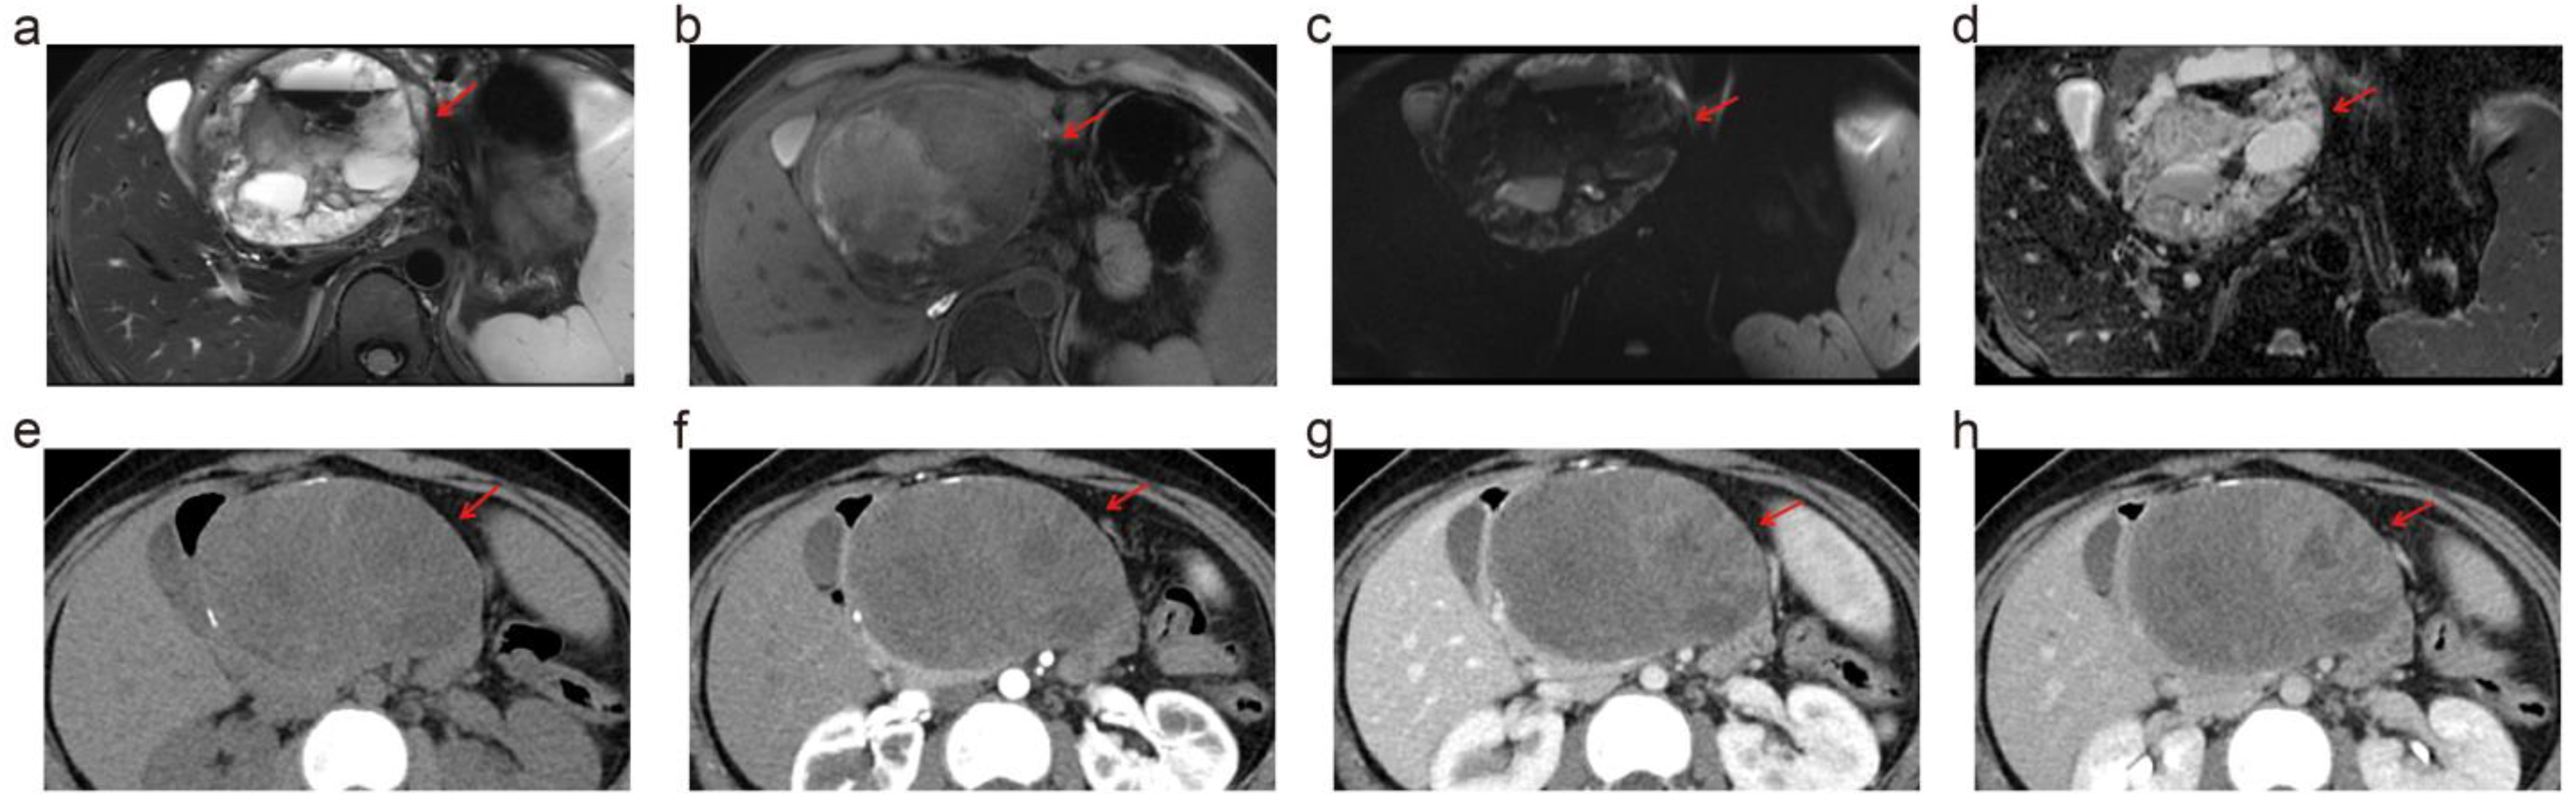

3.3. Depiction of PCL Imaging Features: 5.0 T vs. 3.0 T vs. MDCT